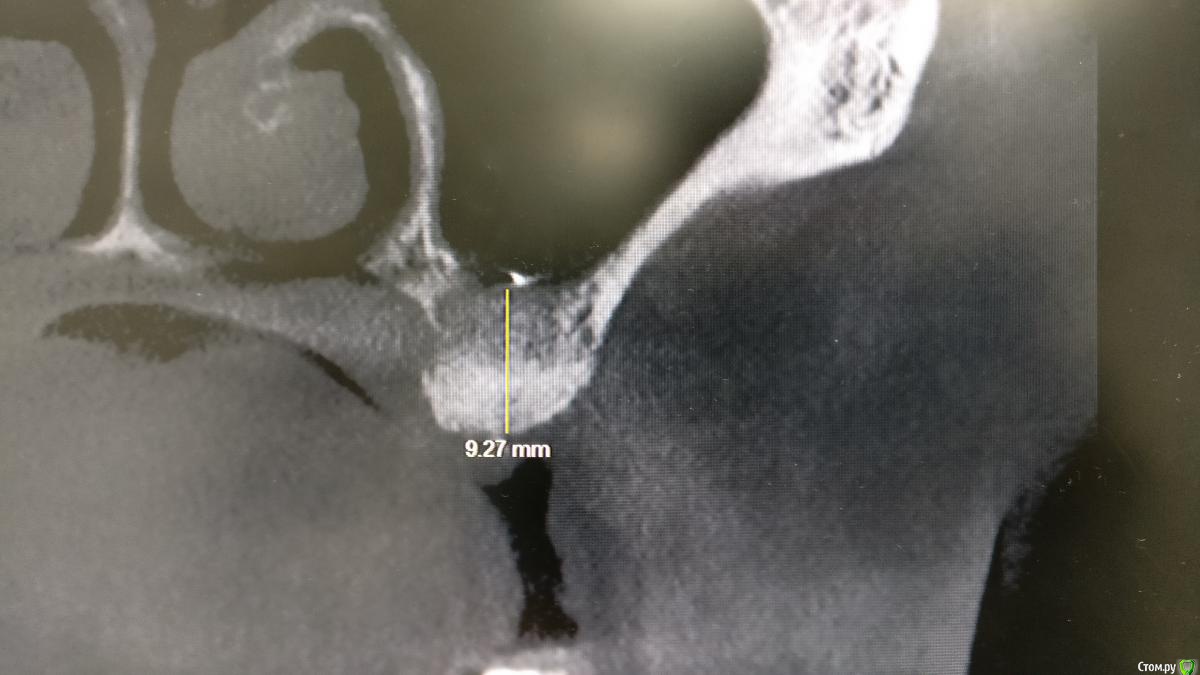

Agent-47 Опубликовано 11 сентября, 2017 Поделиться Опубликовано 11 сентября, 2017 (изменено) Здравствуйте, уважаемые форумчане. У меня вопрос такого характера. 2.5 месяца назад удалил 17 зуб и сразу засыпал лунку био-осс вместе с прф. Возможно ли спустя 2.5 поставить в данное место имплантат? Изменено 11 сентября, 2017 пользователем Agent-47 Ссылка на комментарий

kamranchick Опубликовано 12 сентября, 2017 Поделиться Опубликовано 12 сентября, 2017 Здравствуйте, уважаемые форумчане. У меня вопрос такого характера. 2.5 месяца назад удалил 17 зуб и сразу засыпал лунку био-осс вместе с прф. Возможно ли спустя 2.5 поставить в данное место имплантат?после биосса жду 6 месяцев. часто вкручивал имплантатат в кашу Ссылка на комментарий

syrovovec Опубликовано 12 сентября, 2017 Поделиться Опубликовано 12 сентября, 2017 (изменено) 2,5 точно раноНе раньше 6 мес Изменено 12 сентября, 2017 пользователем syrovovec Ссылка на комментарий

Bier Опубликовано 13 сентября, 2017 Поделиться Опубликовано 13 сентября, 2017 для консервации лунки биооосс очень неподходящий материал. Лучше использовать резорбируемые графты, типа mp3, аллокость или ауто. 2,5 мес рано, ждите теперь не меньше 6ти. 5 Ссылка на комментарий